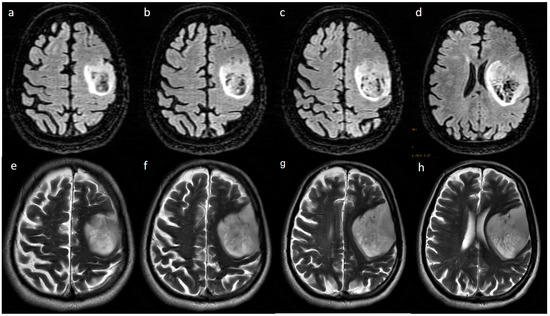

3.2. MRI Parameters of IDH-Wildtype vs. Mutant Phenotype Tumors

| Necrosis | None | 3 (15.8) | 3 (2.3) | <0.001 |

| <25% | 11 (57.9) | 14 (10.9) | ||

| 25- 50% | 2 (10.5) | 35 (27.1) | ||

| >50% | 3 (15.8) | 77 (59.7) | ||

| Edema | None | 3 (15.8) | 3 (2.3) | 0.025 |

| <tumor volume | 11 (57.9) | 68 (52.7) | ||

| Equal to tumor volume | 4 (21.1) | 35 (27.1) | ||

| >tumor volume | 1 (5.3) | 23 (17.8) | ||

| Cysts * | No | 11 (57.9) | 115 (89.1) | 0.001 |

| Yes | 6 (31.6) | 14 (10.9) | ||